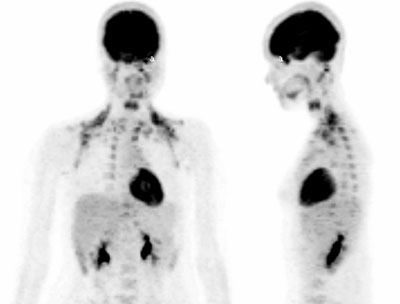

Fig. 2. - Imágenes coronal y lateral de tomografía por emisión de positrones de cuerpo completo. Mujer de 18 años en estudio por lesión naso-sinusal, donde se observa aumento del metabolismo de la [18]FDG en cerebro, área de musculatura oculomotora (a), musculatura cervical, paraclavicular y paravertebral. Asimismo se aprecia aumento del metabolismo de la [18]FDG en ventrículo izquierdo.. Volver

1.6 Musculatura de cabeza y cuello En área de cabeza y cuello, existen muchos músculos que generalmente presentan una captación aumentada de la [18]FDG. La tensión muscular provocada por la ansiedad en el paciente durante la incorporación del radiofármaco es frecuentemente observada en los músculos paraespinales, esternocleidomastoideos y trapecio (fig.2). Estas captaciones se caracterizan por ser simétricas y por una morfología similar a la de los músculos afectados.